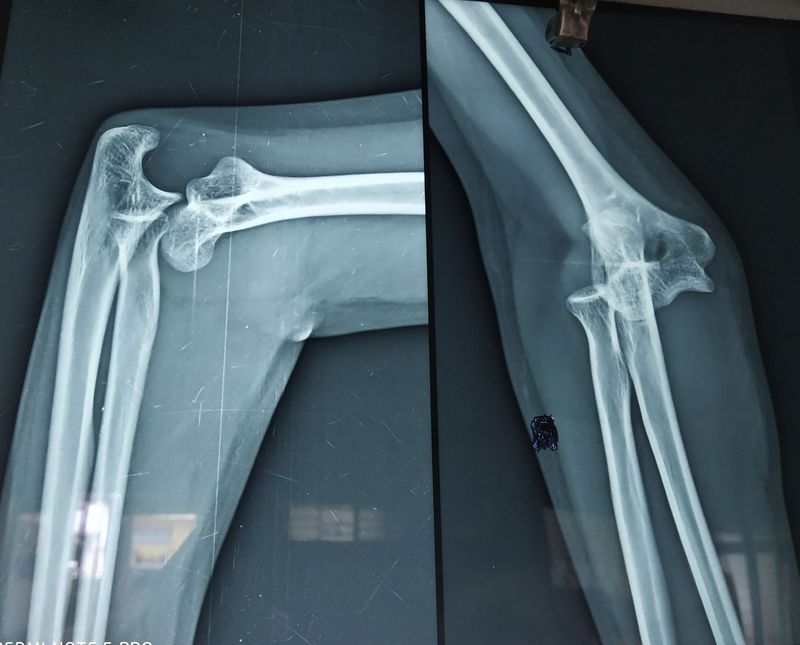

Ms. B having dislocation of left hand while she fall down in bathroom. She is having swelling and redness over the injury area. Left hand is not moveable. While she came to emergency department that time muscle are contracted over the left hand. X-ray is done. After reports Doctors plan for locates the bone by the physical force.locx 2 % given and by the physical force bones are located.Now she is moveable her hand easily. For the pain and swelling medicine given.

U say its looks like knee but where is patella bone? So its conform that its elbow dislocation